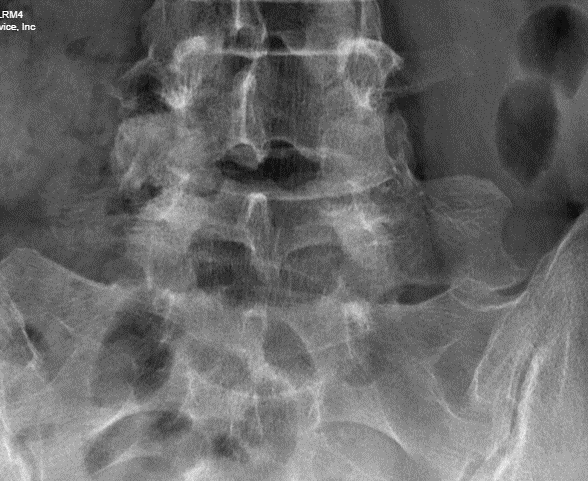

Cropped image taken from an older radiograph of the pelvic in this same patient, confirming the presence of a LSTV variant.

In this case, the level was identified as L5 on DXA based on the shape of the vertebral body superior to it more representative of a typical L4 shape. Review of the patients history found an x-ray of the pelvis taken for an unrelated condition. of hip pain. No mention of a transitional vertebral articulation was mentioned in that report. A cropped section of that radiograph is presented below in Image 2.